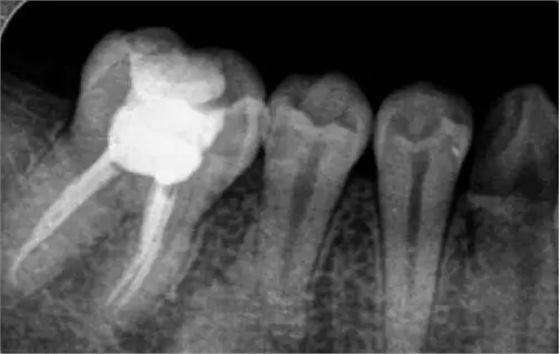

根管治療時,拍牙片是必要的,并且至少要保證3張牙片。

第一張:在治療前,幫助醫(yī)生了解牙根的基本情況,如根管預備是否到位等,并制定計劃。

第二張:在治療中,幫助醫(yī)生了解治療情況,如根管預備是否到位等,并指定下一步的計劃。

第三張:在治療結束后,幫助判定根管填充質量,發(fā)現(xiàn)問題及時補救。